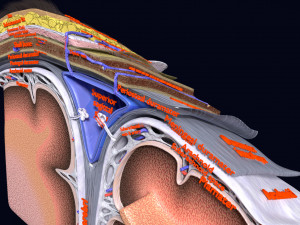

A blend model of brain along with its covering layers (meninges), skull bone and scalp labelled in detail and anatomically precise. The parts depicted are white, gray, pia, arachnoid, dura, bone, skin, fat, aponeurosis, periosteum, falx cerebri and more.

The material is high resolution image textures and normal maps based on non overlapping UVs. The texture and normal maps are packed with the blend file itself.